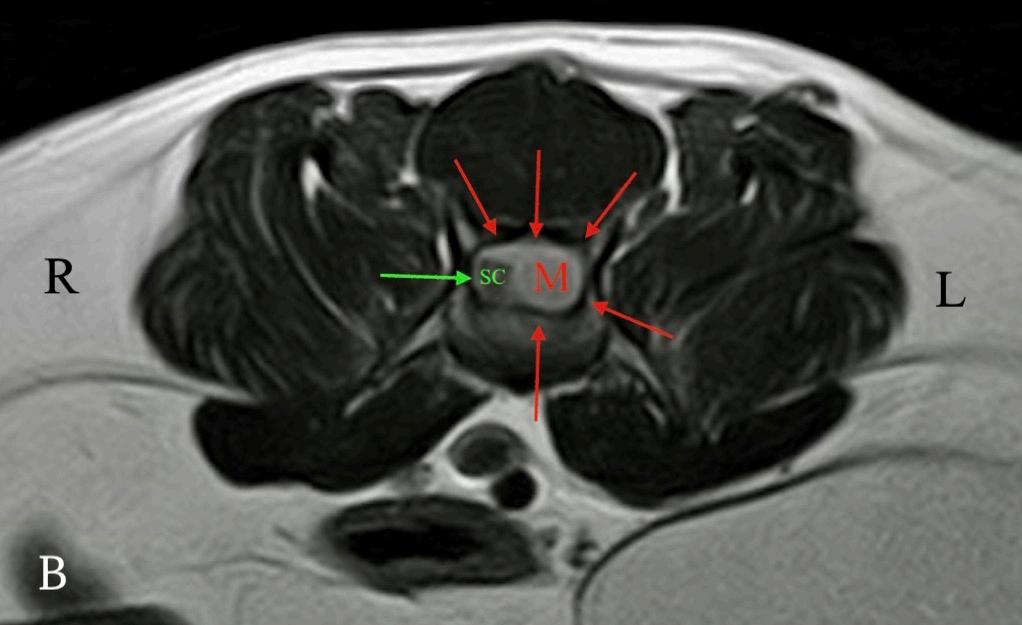

Las pruebas diagnósticas realizadas incluyeron análisis de sangre, radiografía laterolateral de tórax y ecografía abdominal, sin resultar en alteraciones significativas. La serología frente al virus de la leucemia e inmunodeficiencia felina resultó positiva para esta última. En el estudio de resonancia magnética (RM; Fig. 2) de la región toracolumbosacra (Toshiba Vantage Elan 1.5 T: Adquisición de planos transversal, sagital y coronal ponderados en T1 pre y post-contraste intravenoso con gadolinio, así como planos ponderados en T2 y STIR) se cuentan 6 vértebras lumbares, lo cual es compatible con anatomía de transición en la región lumbar, como hallazgo incidental. En el lado izquierdo del canal vertebral, desde el tercio craneal de la vértebra L5 hasta el tercio caudal de la vértebra L6 se encuentra una lesión con aspecto alargado y de base ancha, con márgenes mal definidos e irregulares, distribución posiblemente extradural y/o intradural/extramedular, causando compresión severa de la médula espinal, que aparece desplazada hacia el lado derecho. En cuanto al patrón de intensidad de la señal, este fue hiperintenso de forma homogénea en las secuencias ponderadas en T2 e isointenso en las secuencias ponderadas en T1, con un realce homogéneo y focal en la región media de la vértebra L6. La lesión se extiende parcialmente en el foramen intervertebral izquierdo entre las vértebras L5 y L6 y se aprecia siringomielia leve, que puede ser un proceso secundario a la compresión de la médula espinal por parte de la lesión, más caudalmente a nivel lumbar.

Figura 2. Imágenes de RM postcontraste en las que se identifica una lesión de forma alargada y ancha en su base, con distribución posiblemente extradural y/o intradural/extramedular a nivel de la vértebra L6 (flechas rojas). (A) Secuencia dorsal en STIR. (B) Secuencia transversal en T2. Nótese la compresión severa a la que es sometida la médula espinal (flecha verde). (C) Secuencia transversal en T1 precontraste. (D) Secuencia transversal en T1 postcontraste. M: masa; SC: médula espinal; R: derecha; L: izquierda.